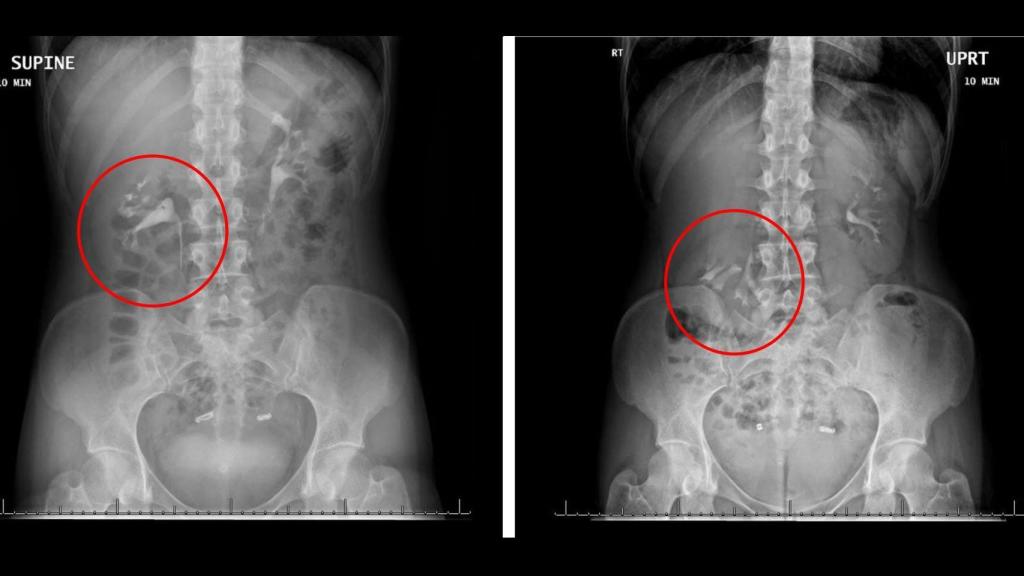

Entre la postura sentada y de pie, el riñón de la mujer se movió 5 cms.

Entre la postura sentada y de pie, el riñón de la mujer se movió 5 cms. BMJ

Se dice que una persona tiene nefroptosis cuando su riñón se desplaza una longitud superior a los cinco centímetros. En el caso de esta chica, las pruebas que le realizaron demostraron que llegaba a superar los seis centímetros, por lo que el diagnóstico era claro.

Según informan en BMJ Case Reports, la prueba clave fue la pielografía intravenosa, un examen radiológico que se usa habitualmente para detectar anomalías en los riñones, la vejiga y la uretra. Los médicos a cargo del caso aseguraron que esta prueba permite conocer a fondo la anatomía dinámica del paciente, por lo que fue esencial para el diagnóstico.